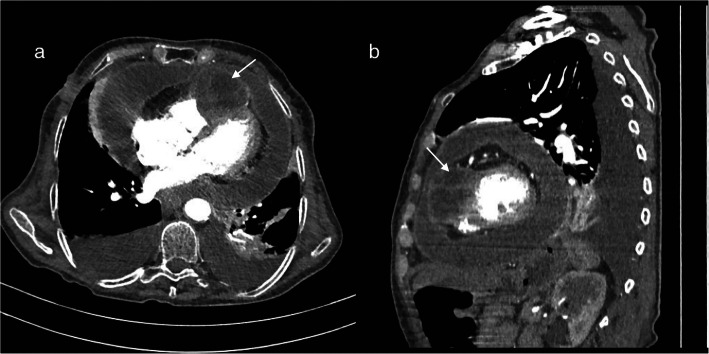

The diagnosis of isolated cardiac hydatidosis involvement was established, and CT scan assessment showed a massive pericardial effusion with hydatid cyst compressing the right ventricle and mild bilateral pleural effusion (Fig. 1) with no other organ involvement.

Fig. 1.

Appearance of massive pericardial effusion with hydatid cyst compressing the right ventricle (arrows) at CT scan. a Transversal view. b Sagittal view